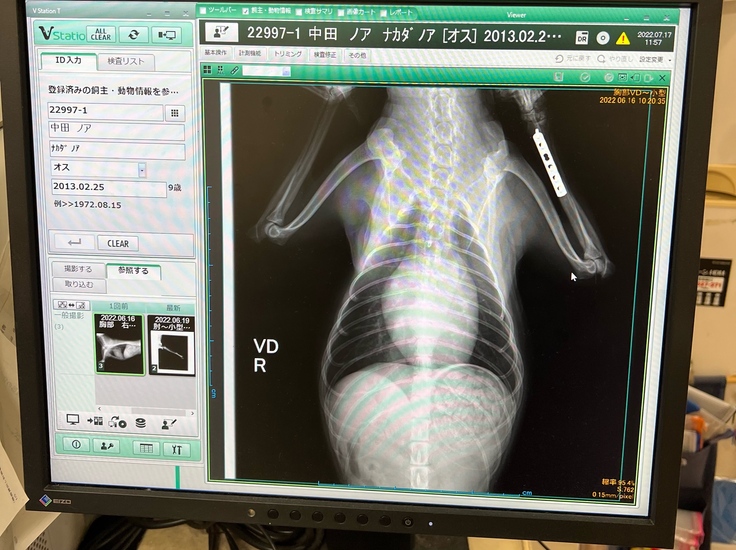

※病院から掲載許諾を得ています(診断名は後から記入していただきました)

※当時未成年だった為病院の名義が父になっています

のあのレントゲン写真になります。※こちらも病院から掲載許諾を得ています